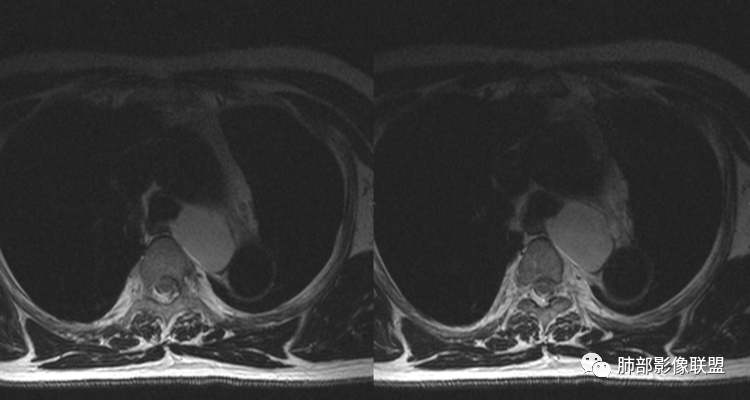

男性,43岁,体检发现后纵隔占位,边缘光整,CT示密度均匀,周围组织受压移位,无钙化囊变及脂肪组织,增强未见明显强化。MRI:T1示肿块信号较肌肉高,T2不均匀高信号。考虑为良性病变,第一是神经节细胞瘤,其次是支气管源性囊肿。

中年男性,无症状,后纵隔肿块,长径大矢状位于横径,质地偏软,塑形,等t1稍长t2,比较均质,增强轻微强化,与脊柱,主动脉,食管脂肪间隙存在,部分层面与脊柱相贴,骨质无改变,周围无肿大淋巴结,考虑神经源性肿瘤,节细胞神经瘤可能大,鉴别心包斜窦,淋巴瘤,淋巴管囊肿。

患者,男,43岁,无意间发现纵隔肿物,无胸闷胸痛,无心慌气短,无咳嗽,无吞咽困难等不适。体检发现的,无症状。

气管、左主支气管后方,食道左侧囊性占位,壁薄且均匀、光滑。气管及左主支气管受压凹陷、变形。

食道也受压变形、移位。